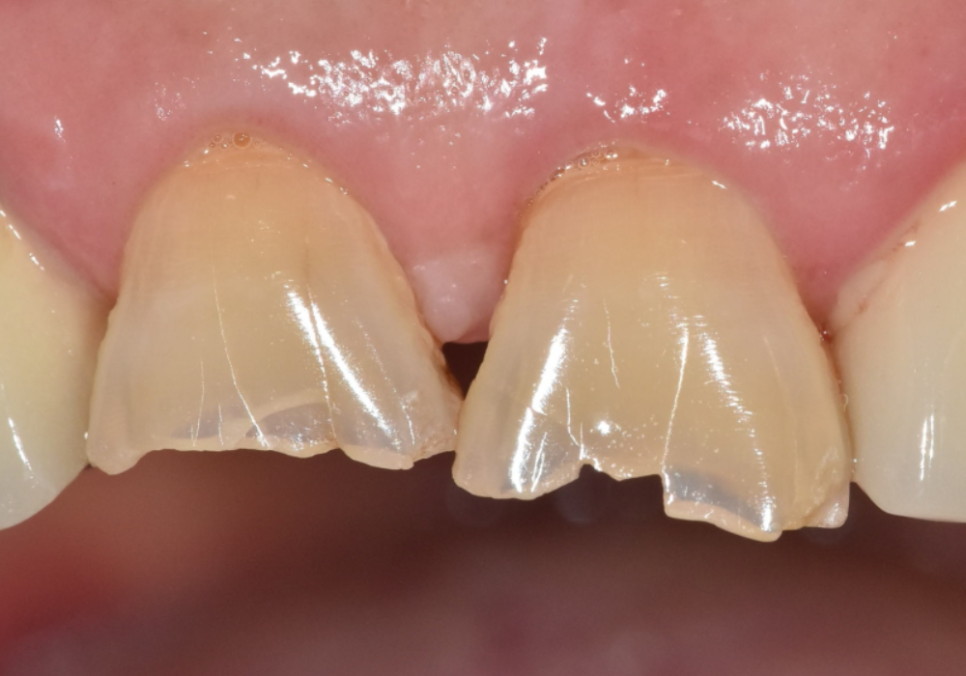

얼마 전 저희 치과를

찾으신 환자분의 사례예요.

왼쪽 위 어금니 두 개(#26, #27)가 동시에

시큰거려서 내원하셨는데요~

입안을 살펴보니 전체적으로

치아가 많이 닳아 있었고,

평소 얼음을 잘 깨 드실 만큼

치아를 강하게 써오신 습관이 있으셨습니다.

정밀 CT를 통해 분석해 보니,

치아에 금이 가 있는게 보입니다.